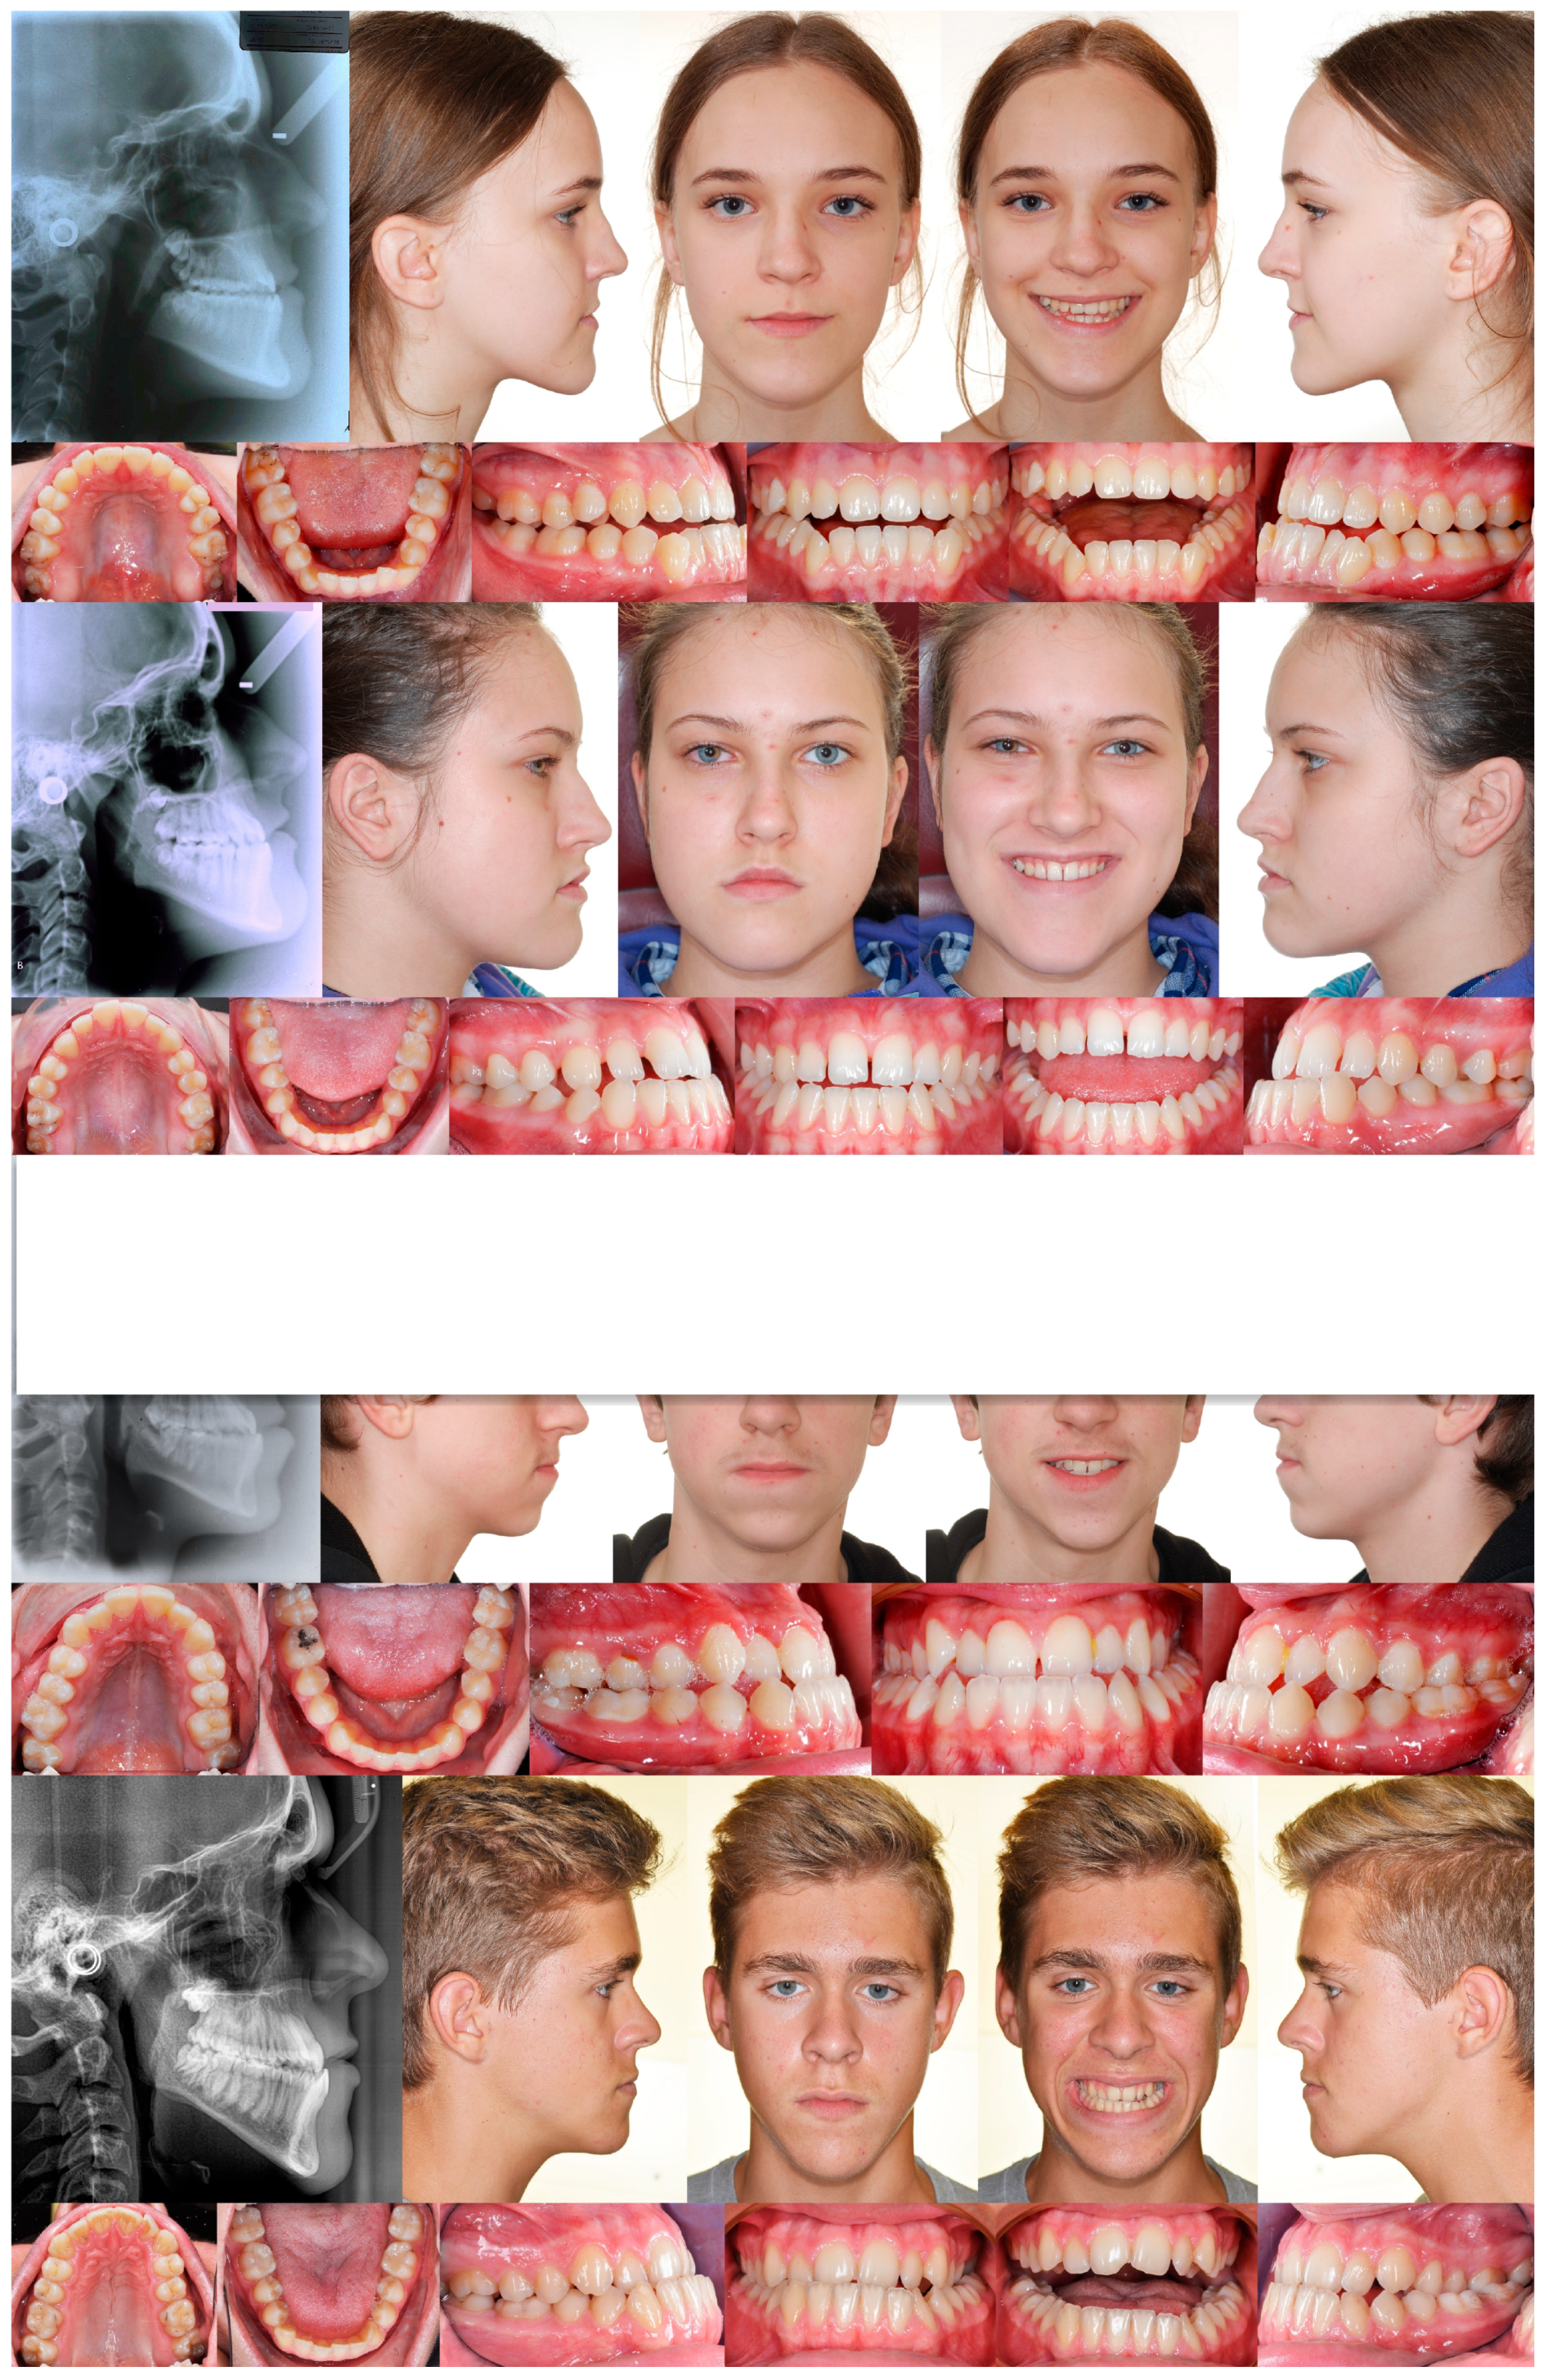

3. The Results of the Treatment